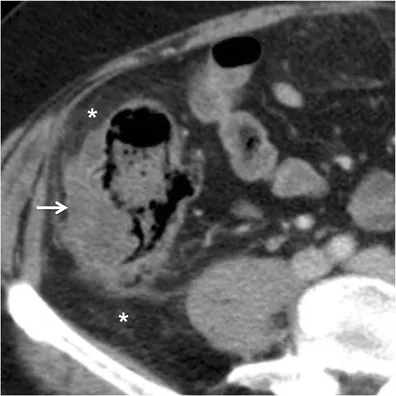

⭐ CT scan is the gold standard and investigation of choice for suspected acute diverticulitis. It confirms the diagnosis and identifies complications.

- Complicated Diverticulitis: Management guided by Hinchey Classification.

- Hinchey Stage I (Pericolic/mesenteric abscess):

- Small abscess (<4cm): IV antibiotics.

- Large abscess (≥4cm): Percutaneous drainage + IV antibiotics.

- Hinchey Stage II (Walled-off pelvic/distant intra-abdominal abscess): Percutaneous drainage + IV antibiotics.

- Hinchey Stage III (Generalized purulent peritonitis): Emergency surgery - Resection and primary anastomosis (R&A) if stable, or Hartmann's procedure.

- Hinchey Stage IV (Generalized fecal peritonitis): Emergency surgery - Hartmann's procedure.

- Hinchey classification guides management of perforated diverticulitis.